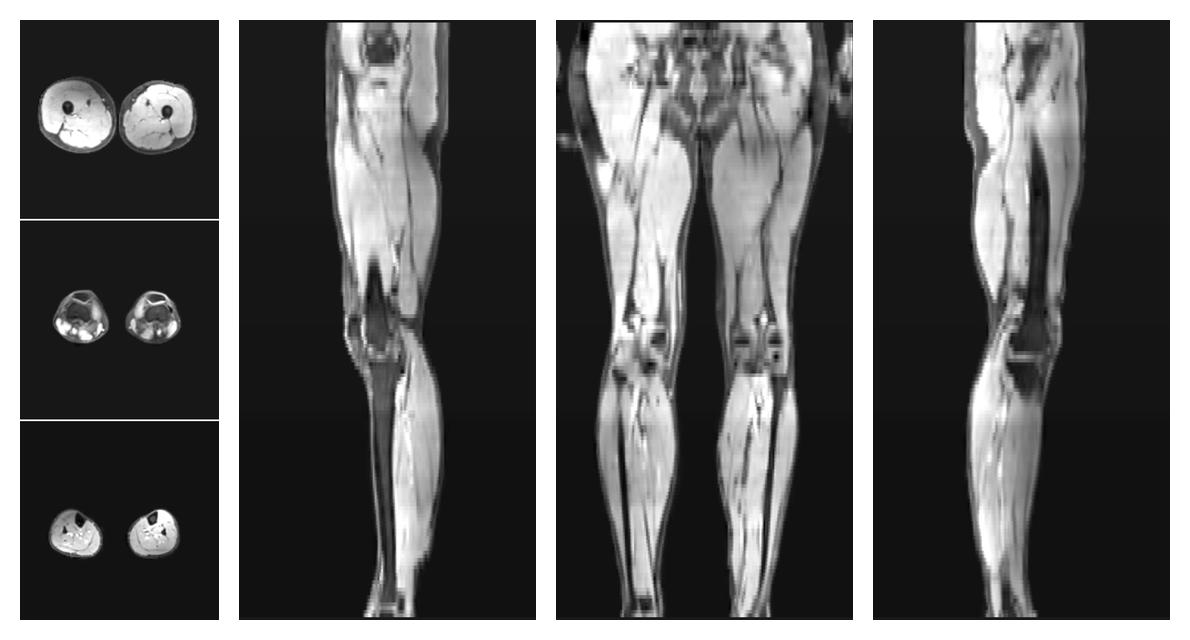

• Water only signal

The water part of the acquired multi-echo spin echo data.